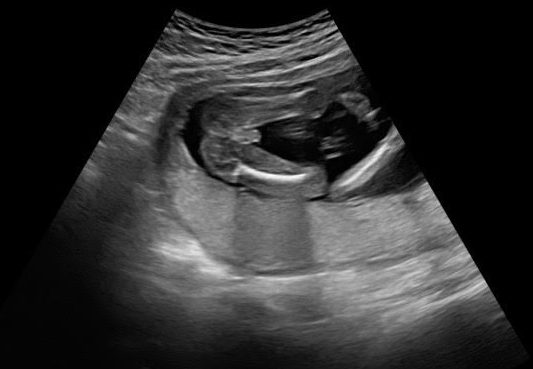

We attended our next appointment when I was 17 weeks with my regular doctor. Before she entered the room, Trent shared how he was finally starting to get over feeling nervous at each appointment, and he was starting to enjoy them, just a little. My doctor did an ultrasound (I get one at every appointment) and was able to confirm that baby was definitely a boy, and everything looked healthy! I then shared with her very casually that I apparently have weird blood, because two blood tests gave me inconclusive results. Thinking her response would be something like “Yup, you just have weird blood, that happens.” I was shocked when she showed some concern. “I don’t want to worry you, but that can be due to problems with the baby or the placenta.” And here we go again with things to worry about..

My body was hot and my mind was racing but also blank as I tried to ingest and understand the many medical possibilities she was listing off. While my initial response was panic and fear, seeing my little bug on that screen, hearing his heartbeat and measurements all being on track, a wave of calm came over me. To conclude our appointment, our doctor apologized and shared that it can also be a lab error and could be nothing! She reminded us that we didn’t want to know genetic testing in the first place, just gender. We now knew the gender, so she left the decision up to us on if we wanted to indulge in further testing or not.

On the way home and the days to follow, I did some research. What an inconclusive blood test can mean, what you can find through genetic testing vs the 20 week anatomy scan, etc. Ultimately, we decided we didn’t want to do further testing. Nothing was going to change the rest of our pregnancy and the love for our baby. We didn’t want the test results in the first place! At our 20 week anatomy scan, the ultrasound tech had zero concerns. Little guy was still measuring and developing great. This was another giant sigh of relief! He was in the 54th percentile and just one day behind my due date.